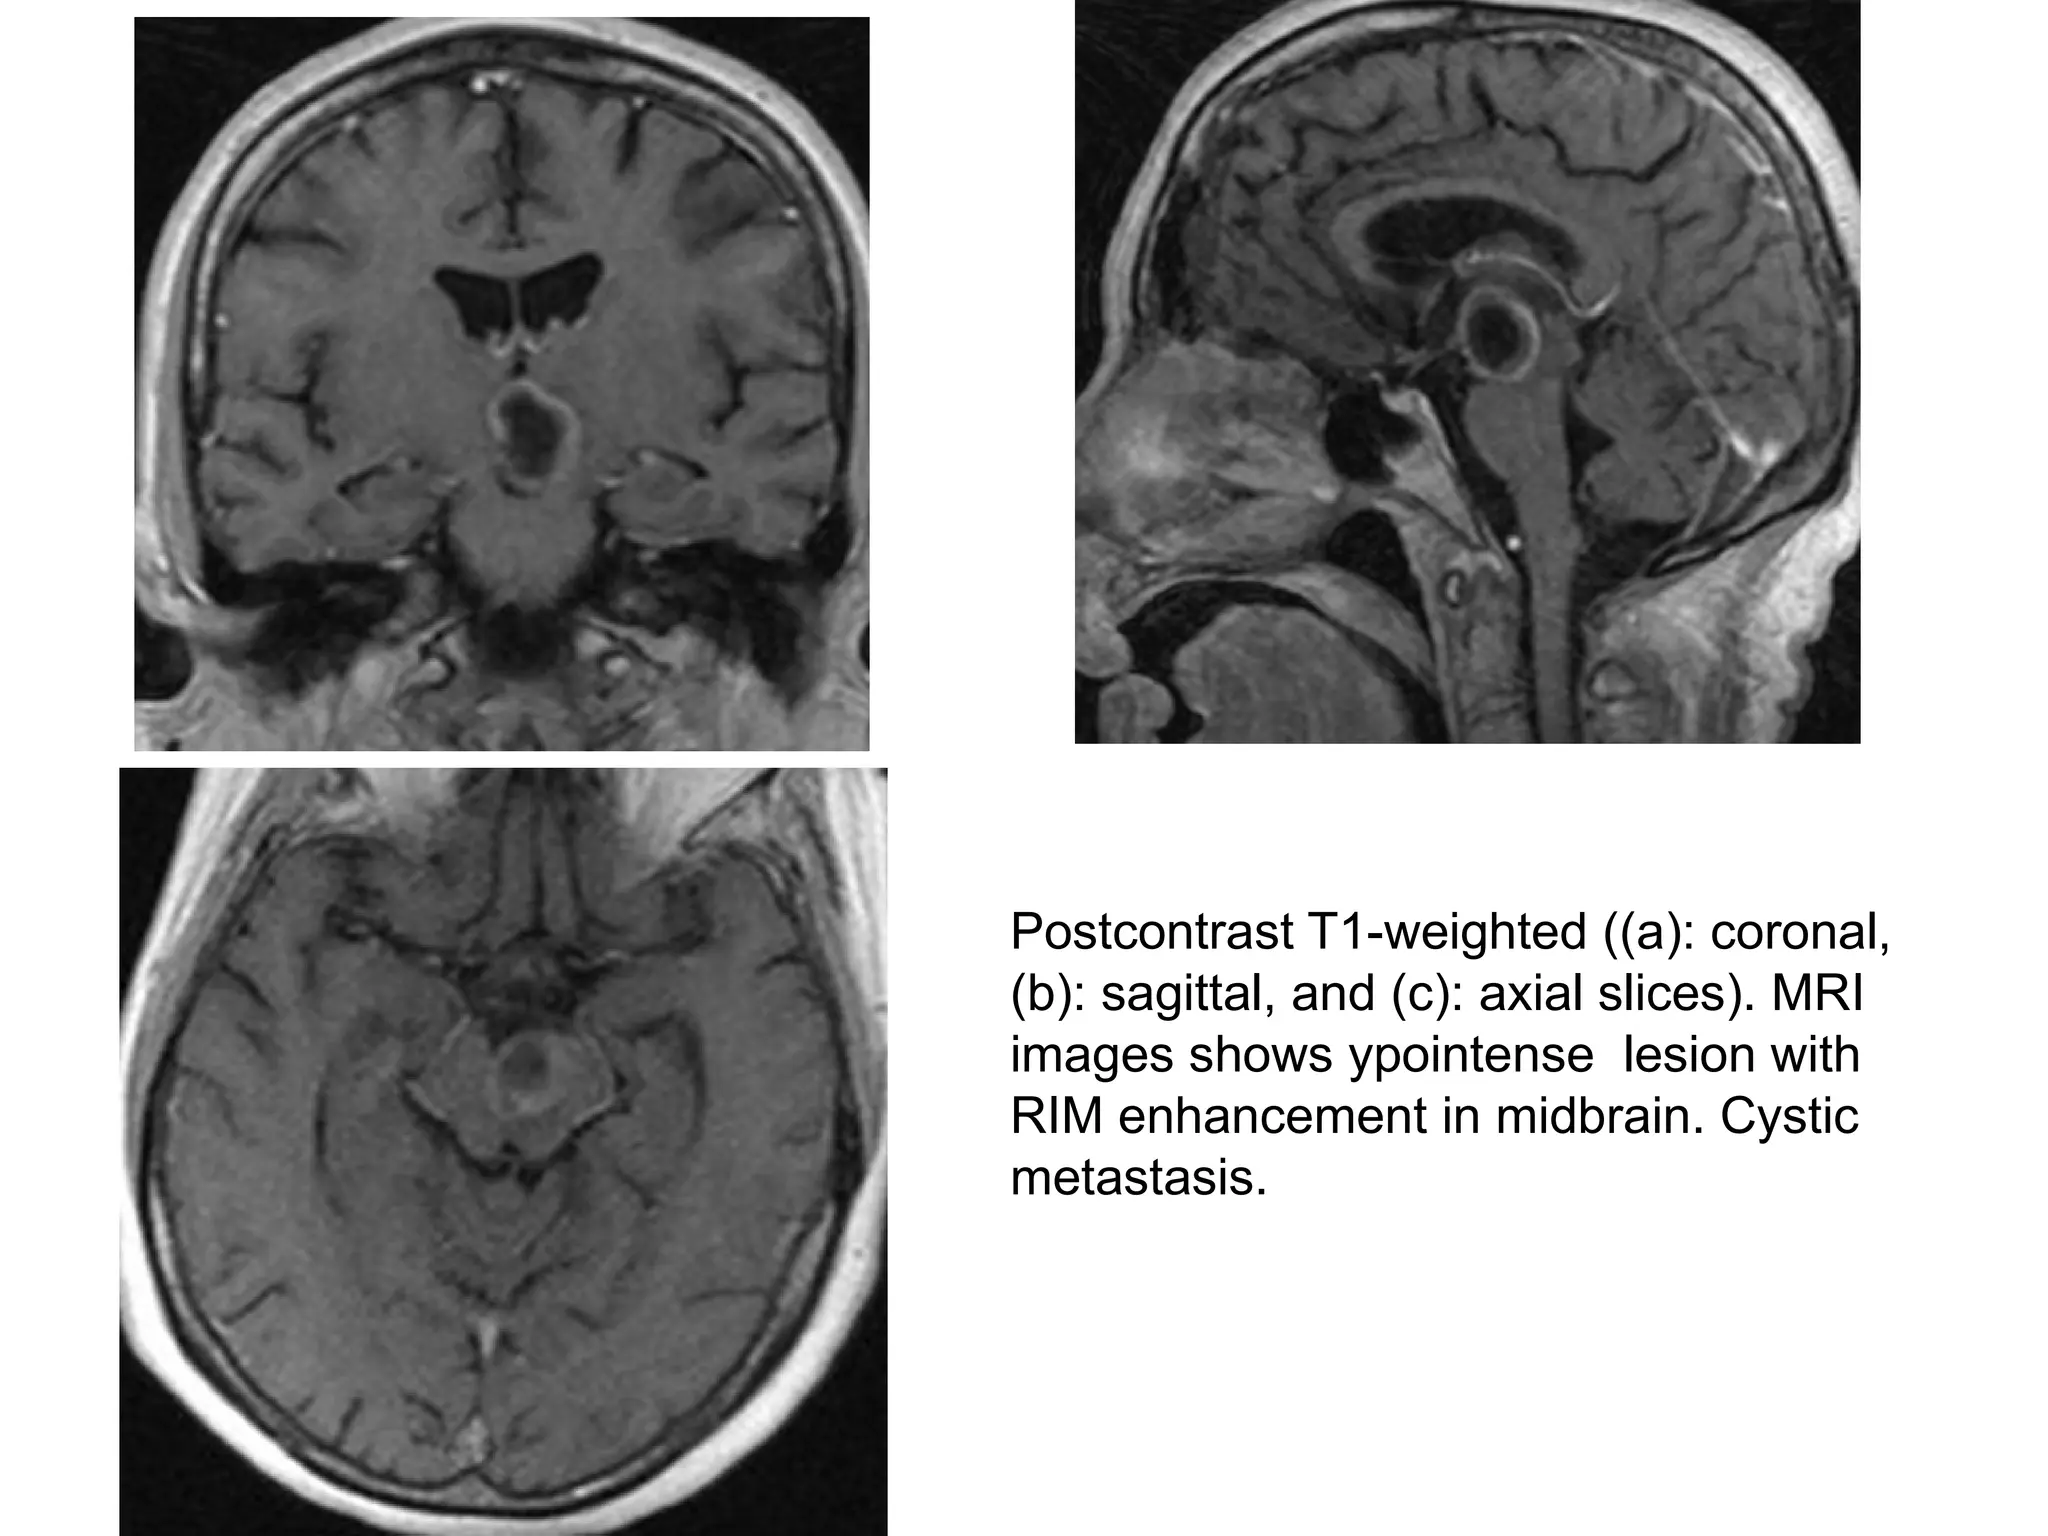

Postcontrast T1-weighted ((a): coronal,

(b): sagittal, and (c): axial slices). MRI

images shows ypointense lesion with

RIM enhancement in midbrain. Cystic

metastasis.